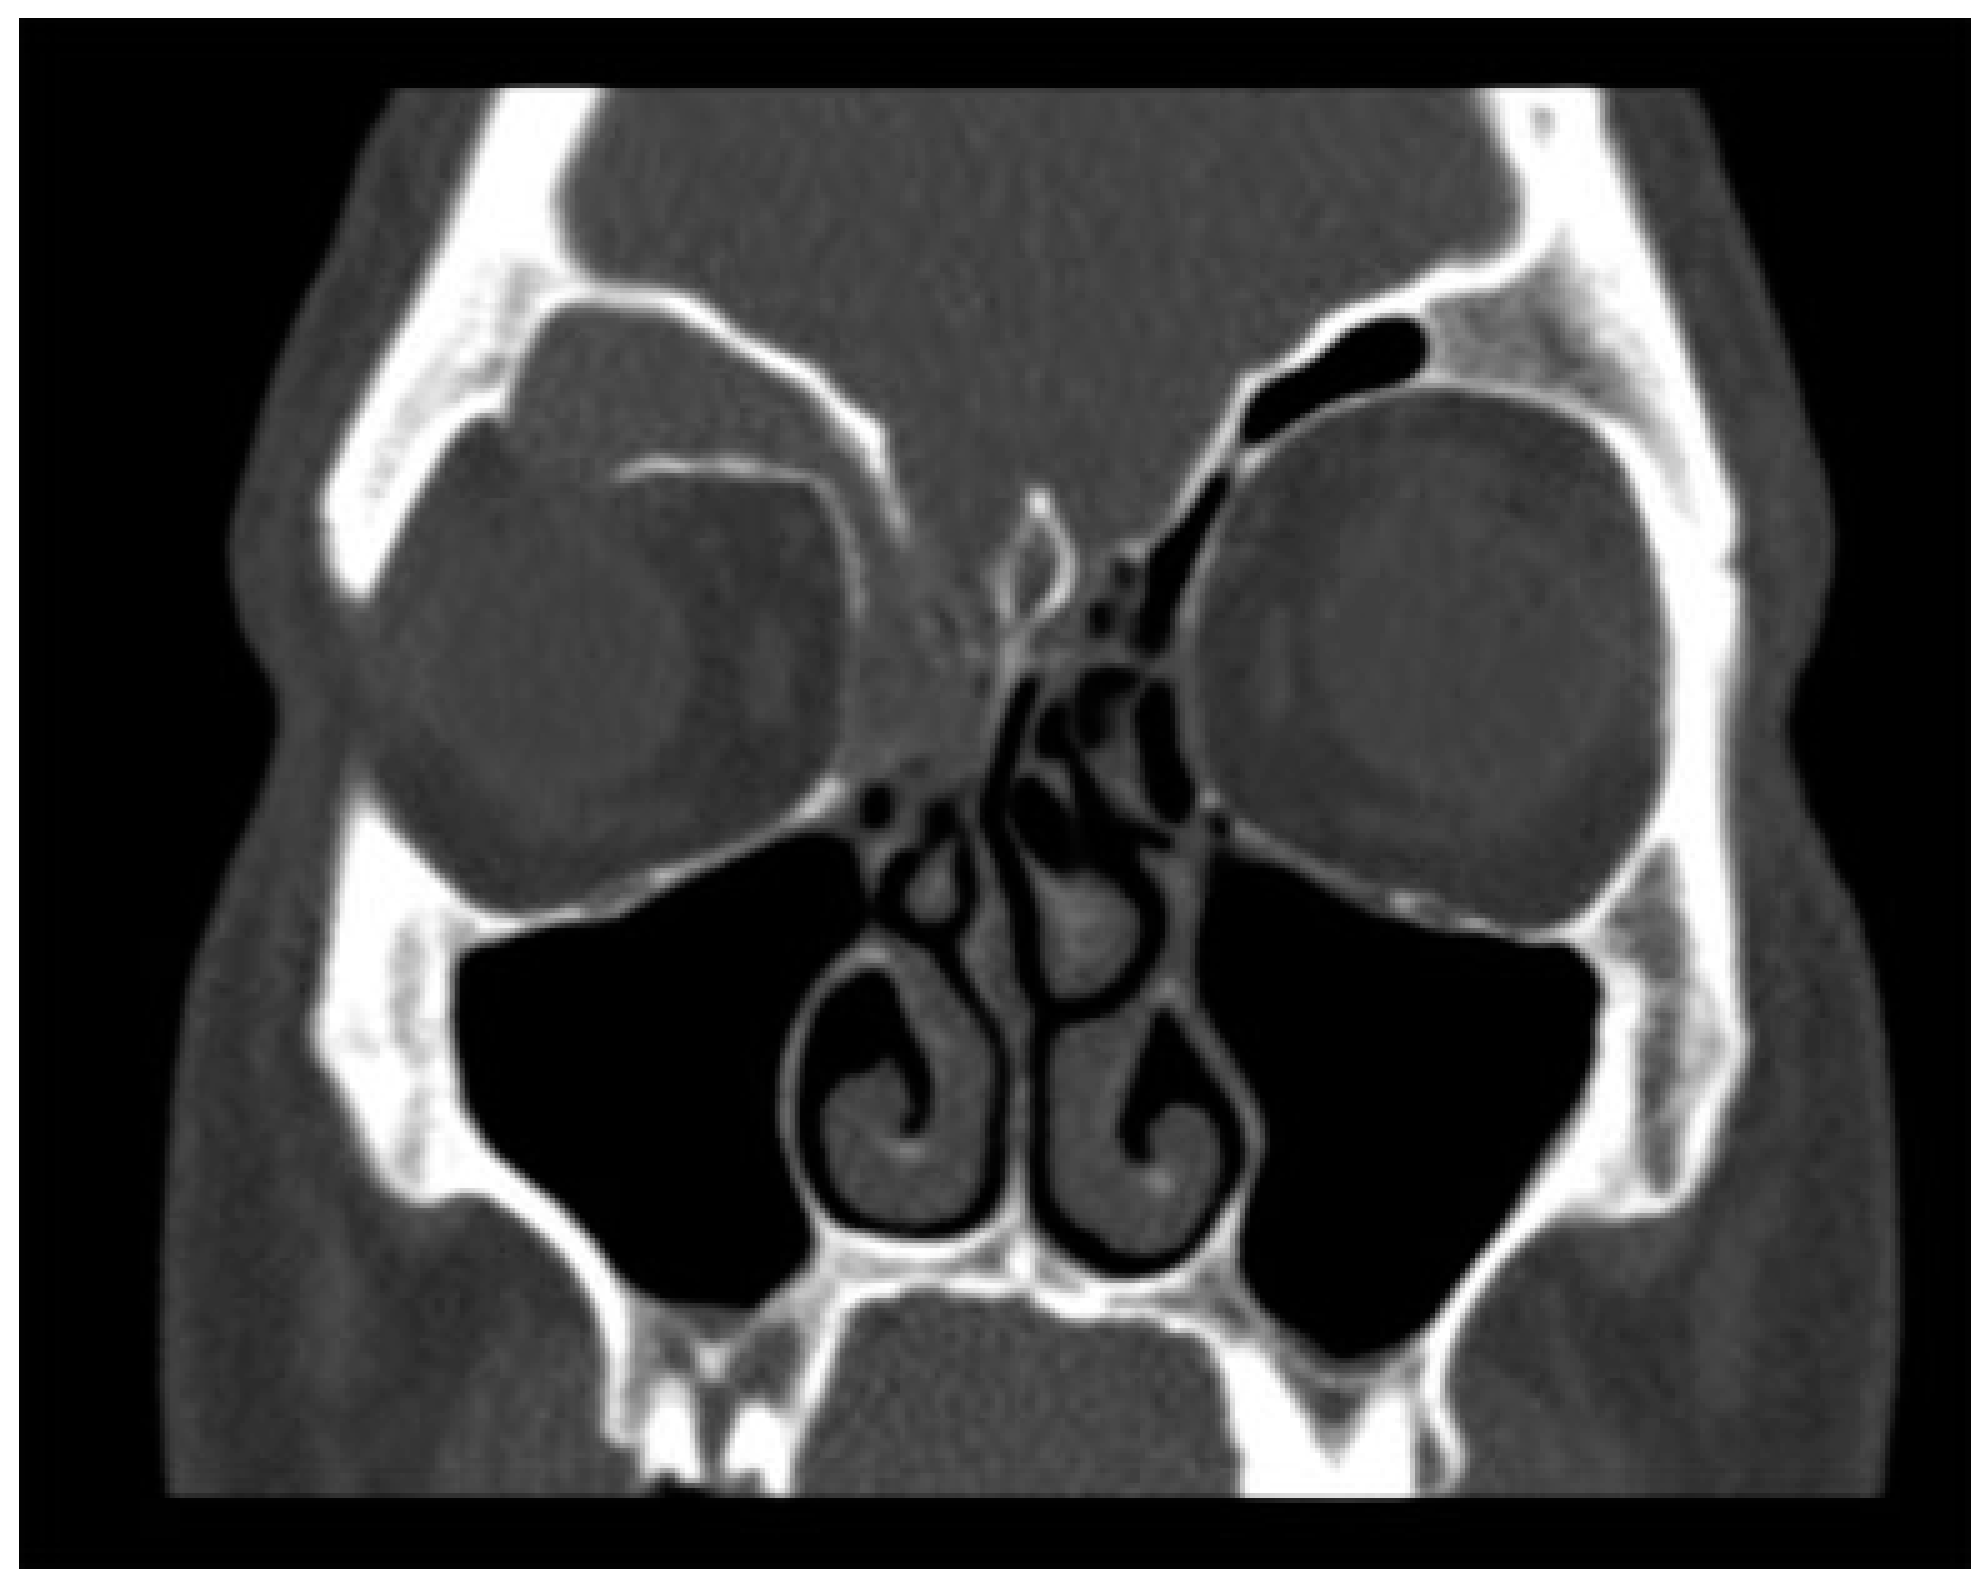

Cranialization necessitates the use of a coronal flap. In addition to the complications associated with a coronal flap, cranialization carries the added early complications of sinusitis, meningitis, persistent CSF leak, and late complications including mucocele formation, CSF leaks, and osteomyelitis (Figure 6).[17,39] The incidence of meningitis after cranialization appears to have decreased over time, with ~50% in early literature, and presently near just 2% (Table 3).[3,16] Yet, less aggressive techniques have been explored to avoid the morbidity of the coronal flap while maintaining a lower rate of infectious complications. One less aggressive technique by Bhavana et al. describes the use of a frontal trephine with endoscopic repair in five patients with fat, bone graft, and fibrin glue in select defects 0.5 cm or less [46].

Figure 6.

CT in the coronal plane demonstrating a right frontal sinus mucocele. The right frontal sinus is completely opacified with associated bony resorption at the superior orbit.